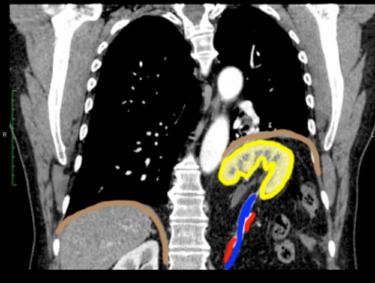

This patient has a congenital diaphragmatic hernia, called a Bochdalek hernia. In this case, it is a very large hernia, with most of the left kidney displaced upward into the chest, stretching the renal artery and vein. The diaphragm on the left is displaced upward. Image B is a select image from Patient A, and Image C shows colored outlines on key structures. Because the embryology of the diaphragm is complex, weak spots may result from incomplete fusion of precursor tissues. If the weakness is posterior in location, a Bochdalek hernia can develop. If the weakness is anterior, a different hernia called a Morgagni hernia can result.